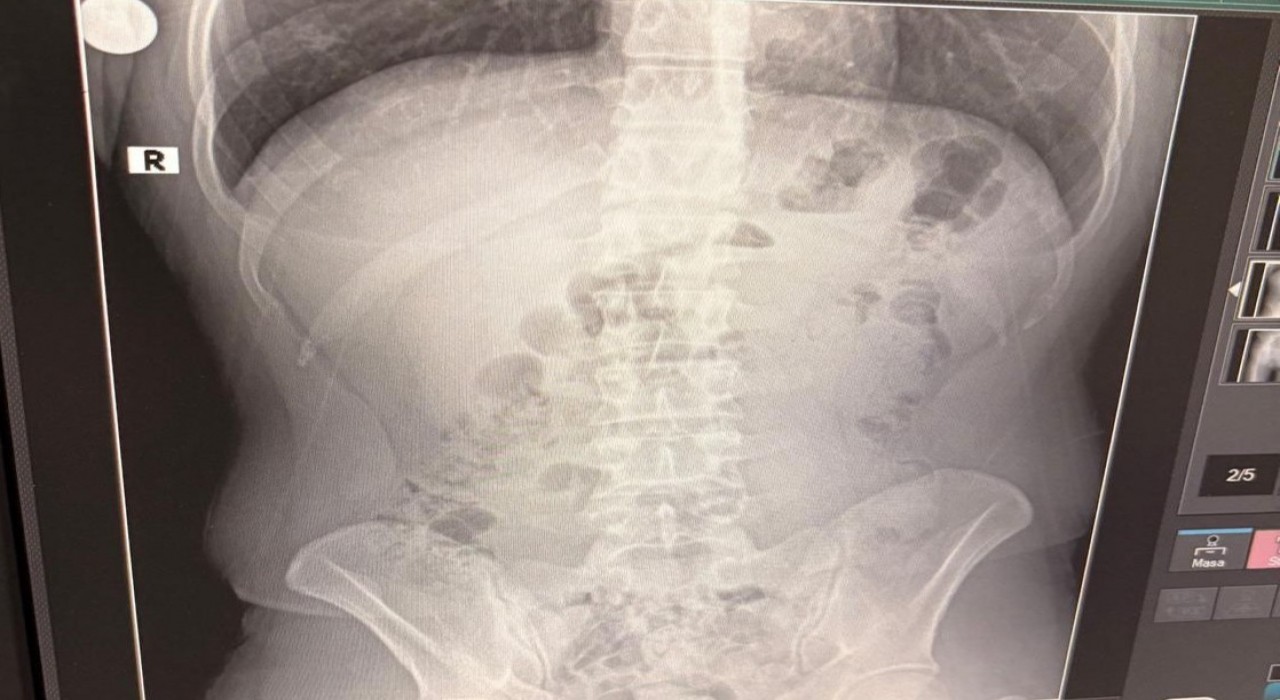

Adreste yapılan arama sırasında ekipler, şüphelilerden birinin üstünde 1 adet kapsül ele geçirdi. Şüphe üzerine tüm şüpheliler hastaneye götürüldü ve yapılan röntgen kontrollerinde 3 kişinin midelerinde kapsül içine gizlenmiş metamfetamin tespit edildi.

Hastanede tedavi altına alınan şüphelilerin vücudundan kapsüller çıkarılırken, adreste ele geçirilenlerle birlikte toplam 1 kilo 516 gram metamfetamin ele geçirildi.